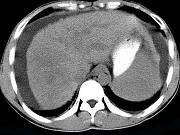

问题 男,35岁,有乙肝病史多年,AFP阳性,影像检查如图,最可能的诊断是()

选项 A.肝硬化腹水 B.肝血管 C.肝脓肿 D.肝癌、硬化腹水 E.肝硬化,结节性增生

答案 D